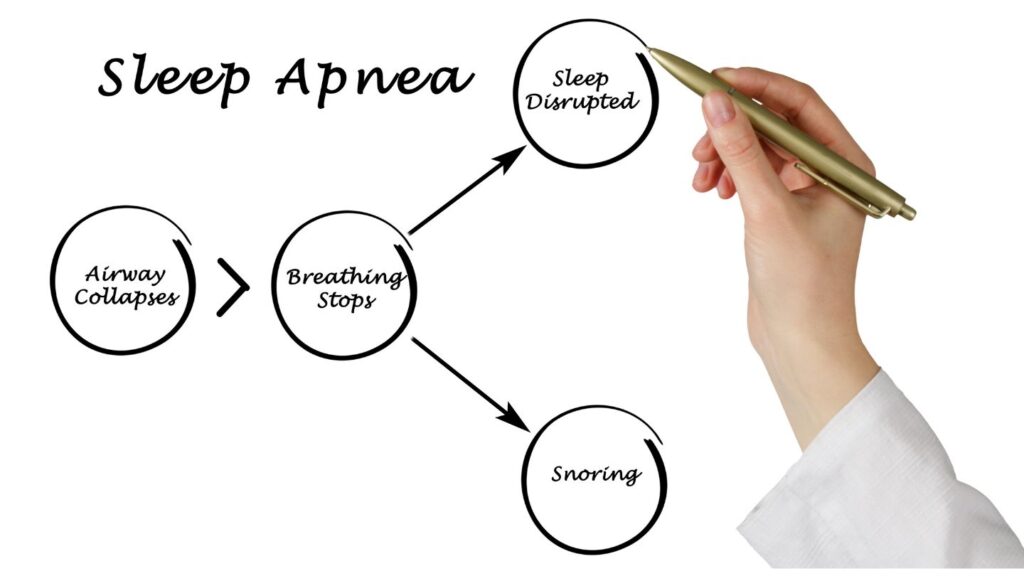

Sleep apnea is a chronic condition in which your breathing is repeatedly stopped and started while you sleep. This can happen hundreds of times a night. Sleep apnea is a serious condition that can lead to a number of health problems.

An apnea is a cessation of breath for more than 10 sec. In OSA, the airway is either completely or partially blocked by the tongue or soft tissue in the back of the throat. This leads to interruption in breathing that causes drops in oxygen level which inturn increases the carbon dioxide levels, when the body detects this it responds by sending signals to the brain that awaken the person from sleep. This can happen every few minutes throughout the night. 70% of OSA sufferers are under diagnosed.

Snoring and Obstructive Sleep Apnea: Sleep apnea and snoring are two very common sleep disorders. If you have either of these conditions, what kind of treatment options are available to you? A permanent dental sleep solution or a temporary CPAP machine . When it comes to sleep apnea, this condition may cause your airway to vibrate, which can result in noises such as gasps, gurgles, snorts, groans, or chokes. It can affect your sleep. Get some insight as to whether or not you’re experiencing an obstructive sleep disorder like OSA. Not everyone who snores has sleep apnea, and not everyone who has sleep apnea snores. The main indication is how you feel during the day. Normal snoring doesn’t interfere with the quality of your sleep as much as sleep apnea does, so you’re less likely to suffer from extreme fatigue and sleepiness. Sleep apnea is a critical condition that will affect your health very badly. It directly affects your airway and oxygen supply.

How sleep apnea occurs and its complications

How Sleep Apnea Occurs